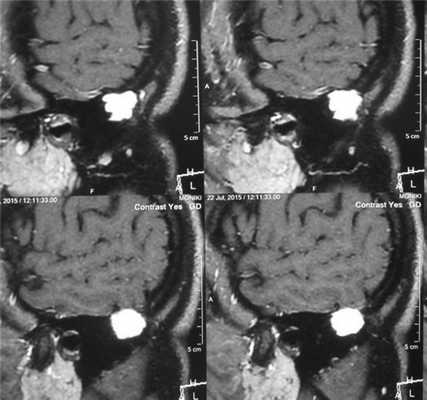

При тональной пороговой аудиометрии (ТПА) слух в пределах нормы с обеих сторон.

По данным МРТ височных костей: в задних отделах сосцевидного отростка слева имеется образование, имеющее слабогетерогенный изоинтенсивный МР-сигнал в режимах T1 и T2 BИ, содержащее сосудистые структуры. Определяется четкая косная деструкция на границе с бороздой сигмовидного синуса (рис. 1). Отсутствует связь образования с оболочками мозга. Размеры образования — боковой до 15 мм, переднезадний — до 18,5 мм, каудокраниальный — до 19,5 мм. По данным МРТ образование левого сосцевидного отростка, активно накапливающее контрастный препарат, рекомендовано дифференцировать с ксантогранулемой, лангергансоклеточным гистиоцитозом и эозинофоильной гранулемой.

Рис. 1. МРТ височных костей. Боковая проекция слева. В задних отделах сосцевидного отростка образование со слабогетерогенным изоинтенсивным сигналом. Размеры образования — боковой до 15 мм, переднезадний — до 18,5 мм, каудокраниальный — до 19,5 мм.